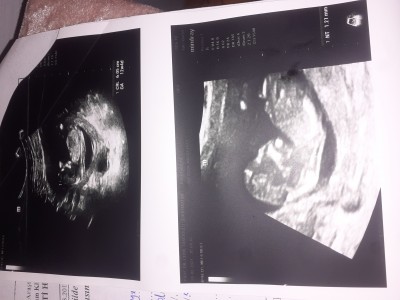

Selamlar arkadaslar ben gecen hafta ikili testi yaptim doktor dun bana once bi sorun yok dedi sonra riskli dedi sorun ne dedigimde suan kafam calismiyo bu saatlerde gibi bi saçmalık duydum doktordan tekrar gotmeyi dusunmuyorum guvenemem artik doktora siz anliyosanz yardi edermisiniz

Gebelik haftası 13+2 haftalik

Sonuclarinda Dusuk risk yaziyor canim hep  icin rahat olsun Allahin izniyle